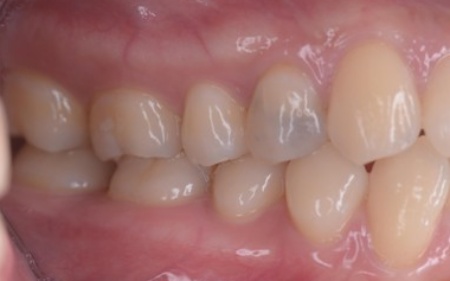

10代女性 乱れた歯並びと噛み合わせをワイヤー矯正で改善した症例

「歯並びが悪い。とくに八重歯が気になる」とご相談いただきました。

拝見したところ、上下の前歯を中心に、歯が正常な位置からずれたりねじれたりしてデコボコに生えている状態でした。

矯正治療終了後は、歯が元の位置に戻ろうとする後戻りを起こすリスクがありますが、治療後15年たった現在も後戻りすることなく、正しい歯並びを維持しています。